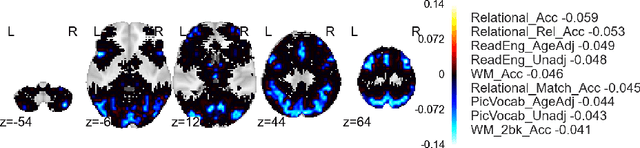

Approximate inference via information projection has been recently introduced as a general-purpose approach for efficient probabilistic inference given sparse variables. This manuscript goes beyond classical sparsity by proposing efficient algorithms for approximate inference via information projection that are applicable to any structure on the set of variables that admits enumeration using a \emph{matroid}. We show that the resulting information projection can be reduced to combinatorial submodular optimization subject to matroid constraints. Further, leveraging recent advances in submodular optimization, we provide an efficient greedy algorithm with strong optimization-theoretic guarantees. The class of probabilistic models that can be expressed in this way is quite broad and, as we show, includes group sparse regression, group sparse principal components analysis and sparse canonical correlation analysis, among others. Moreover, empirical results on simulated data and high dimensional neuroimaging data highlight the superior performance of the information projection approach as compared to established baselines for a range of probabilistic models.